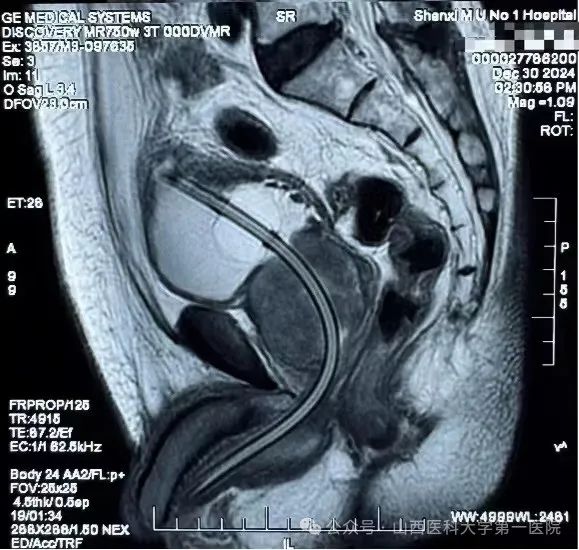

老人来自山西灵石,患慢性阻塞性肺病10年,因“胸憋气短加重7天”入住呼吸与危重症医学科,出院后又因“急性尿潴留,持续肉眼血尿”再次入住急诊医学中心,接诊医生给与留置尿管,持续膀胱冲洗。既往病史还包括:13年前因冠心病行冠状动脉支架置入术(3枚),后未复查(住院后复查发现仍有两支病变,最多狭窄80-90%),长期口服抗血小板药物,偶有背部不适,活动后明显气喘,长期卧床。前列腺核磁提示前列腺巨大,约109ml(正常人约20-30ml)。此前,患者就因反复出现急性尿潴留、血尿而四处求医,因身体状况差,无法耐受麻醉及长时间手术而选择药物治疗,但效果不明显,生活质量极差。